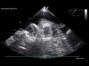

large atrial tumor: filling the whole right atrium.apical view